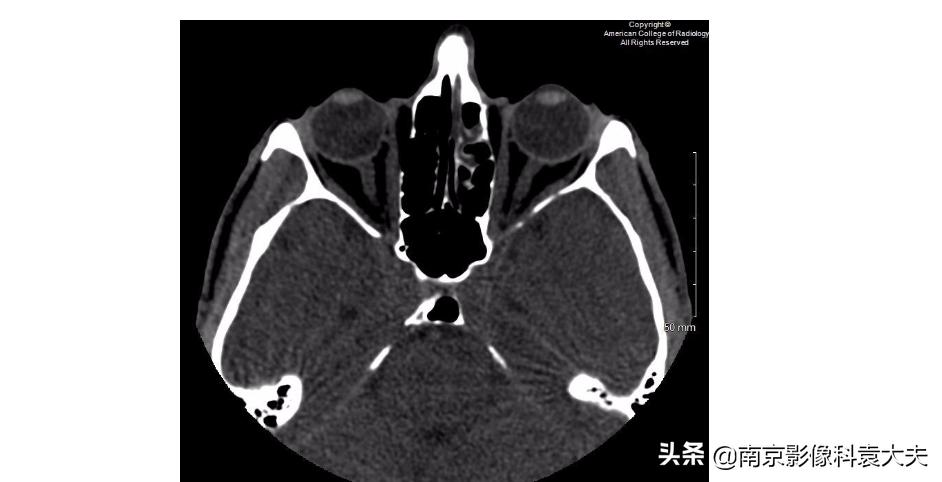

以下补充的眼眶CT图像显示有哪一种异常?

B:右侧眼球外侧的高密度提示出血,这往往是眼外伤的直接征象。

D:一个小的眼外异物位于右侧眼球的表面,它是患者角膜裂伤的一个潜在原因。